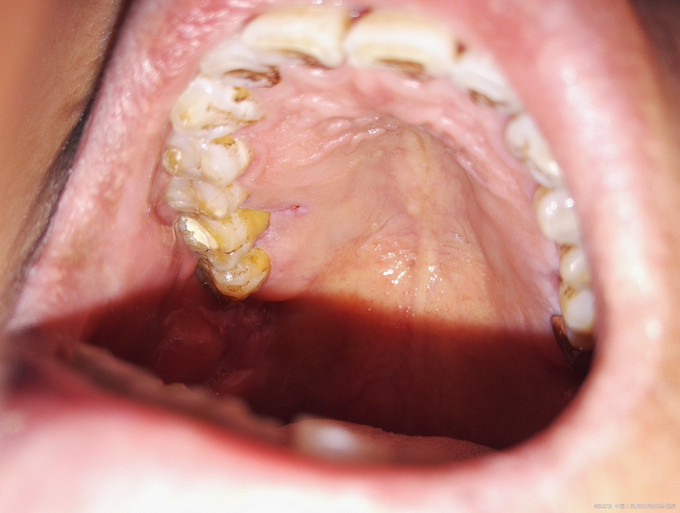

检查:16牙冠完整,牙龈红肿,腭侧可见一窦道,PD=13-5mm,叩痛(++),松动II度。 X线示:16髓腔部分钙化,根管影像不清晰,未见根充影像,根尖周大面积低密度影,近远中根周膜增宽。

诊断:16牙周牙髓联合病变(逆行性牙髓炎) 治疗计划:16RCT+牙周基础治疗+改良翻瓣术 初诊:常规局麻下开髓揭顶,髓腔钙化,少量髓石,超声探查根管,拔髓,根管较细,疏通,封EDTA,一周后复诊。 复诊1:去暂封,继续探查根管,P、MB通畅,DB根尖区钙化,电测根长:P=MB=17.5mm,DB=15mm,EDTA下手扩+机扩+protaper根备至F2,生理盐水+双氧水反复交替冲洗,干燥,CP棉球+ZOE暂封,约日复诊。 复诊216消毒,局麻下洁治,刮治,小翻瓣术,搔刮出大量肉芽组织及少量牙石,根面平整,浓替硝唑冲洗,复位,OHI,约日复诊。 复诊3:腭侧窦道基本愈合,去暂封,超声荡洗,干燥,试尖可,糊剂+热牙胶根充,棉球+ZOE暂封,2周后复诊树脂充填。 复诊4:复诊常规树脂充填,腭侧窦道愈合(忘记拍片子,太遗憾,但是患者1个月后会过来复查)。